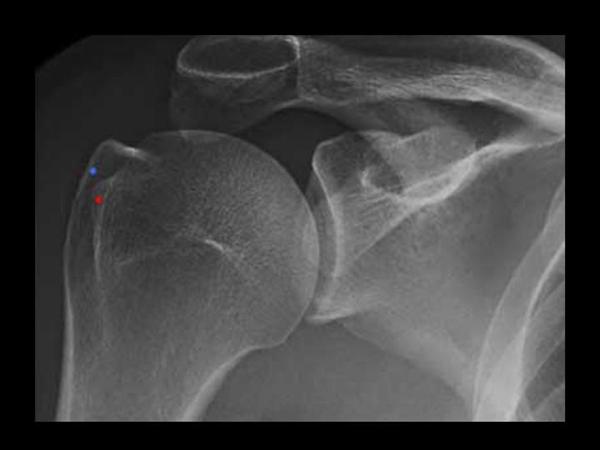

2. True shoulder AP

Glenohumeral joint space, DJD, and proximal migration of humerus